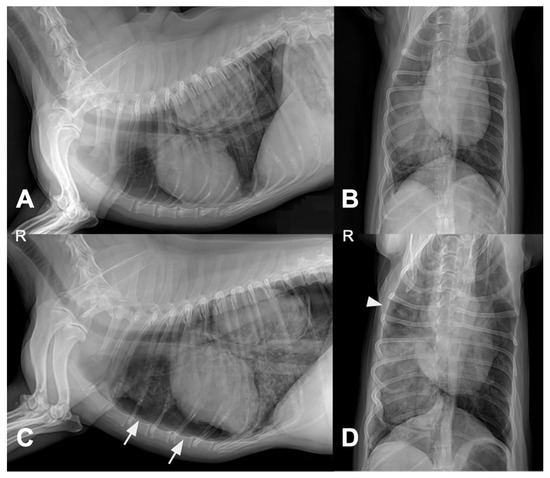

Computed Tomographic and Ultrasonographic Features in Three Dogs with Infected Uterus Masculinus and Concurrent Genital Neoplasia

Uterus masculinus is a rare disorder of sexual development in males, characterized by the presence of tubular female genitalia. Diagnostic imaging reports of infected uterus masculinus are limited. We describe the ultrasonographic and computed tomographic findings in three dogs, all presenting with abdominal distension, pain, and systemic infection. Imaging consistently revealed a fluid-filled, bicornuate structure arising from the prostate. In two dogs, the horns extended through the inguinal rings to the scrotal testes; in the third, with a prior left orchiectomy, both horns were intra-abdominal, the right ending in a peritoneal mass. Surgery and histopathology confirmed infected uterus masculinus, with Escherichia coli isolated from urine in all dogs and from the structure in two. Two dogs had Leydig cell tumors, one with concurrent uterine neoplasia; the third had an ovarian or ovotesticular granulosa cell tumor. Although rare, infected uterus masculinus is potentially life-threatening and should be considered in male dogs with abdominal pain, distension, or systemic infection. This is the first case series describing combined ultrasonographic and tomographic features of infected uterus masculinus, including novel findings such as cervix-like mural narrowing and fluid–fluid levels. It is also the first imaging description of an ovarian or ovotesticular tumor in a dog with uterus masculinus. Full article

Figure 1